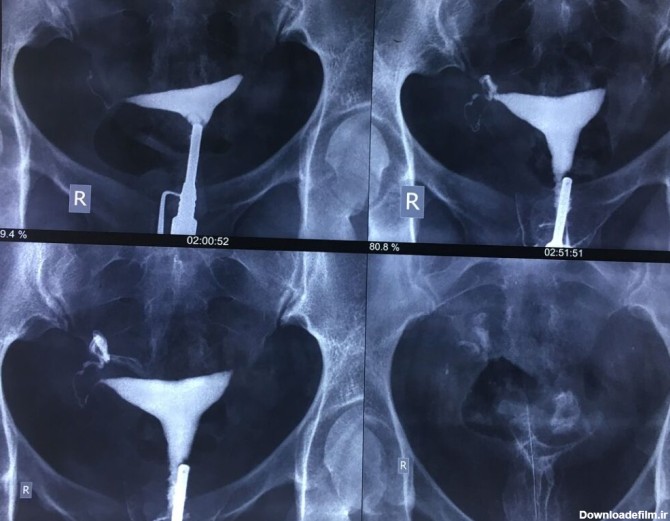

برای بررسی علت تأخیر باروری، باید سلامت اندامهای تولید مثل مورد ارزیابی قرار گیرند؛ یکی از روشهای تشخیصی که برای بررسی رحم و لولههای رحمی درخواست می شود، هیستروگرافی است. با این تست، پزشک از وضعیت داخلی رحم و لوله های رحمی مطلع میگردد و با توجه به نتایج حاصل از تست، در مورد نحوه درمان تصمیم خواهد گرفت. انجام این تست در ارزیابی ناباروری بسیار مهم است.

عکس رنگی رحم با بیهوشی یا بدون درد یکی از خواسته های بانوان است که از حدود شانزده سال پیش توسط دکتر مقدس زاده در مرکز پرتو طب آزما قم در حال انجام است.

الزاما در عکسبرداری رنگی رحم فرد بیهوش نمیشود، بنا به صلاحدید پزشک و انتخاب بیمار تصمیمگیری میشود که آیا بیمار تحت بیهوشی قرار گیرد یا خیر؟